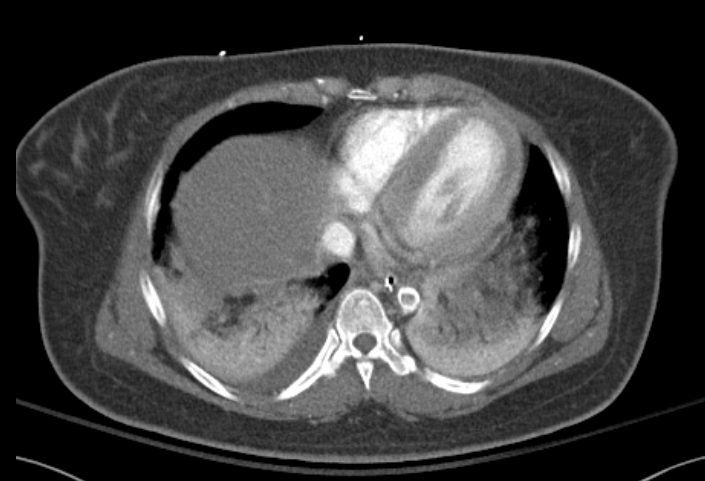

CT chest abdomen pelvis showed a calcified thrombus in the suprarenal aorta consistent with coral reef aorta.

Discussion: Coral reef aorta is a rare vascular disease of the that is characterized by rough, calcified plaques that extend into the lumen resulting in decreased vascular flow. These plaques are often described similar to bony lesions because of their high percentage of calcium